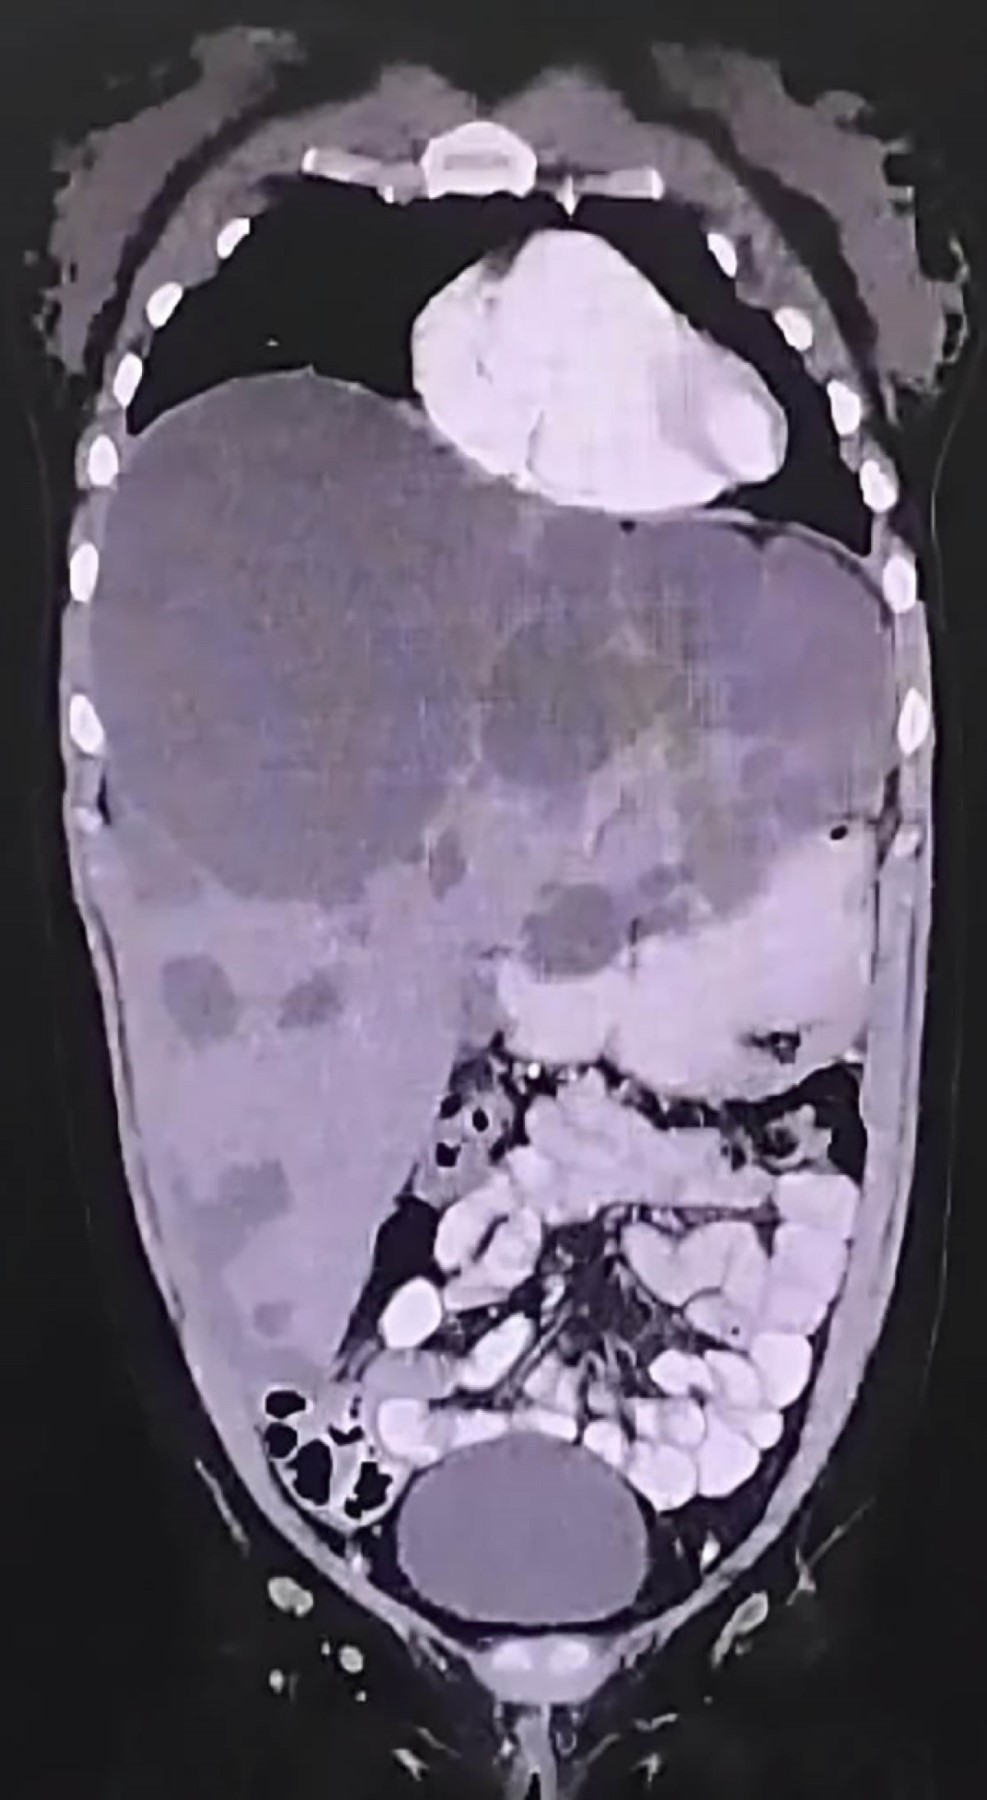

Polycystic liver disease: a case report with laparoscopic intervention

Introduction: polycystic liver disease is a rare hereditary condition which makes up 3% of benign liver lesions that results in liver cysts due to mutations in fluid transport proteins and hepatic epithelial cell growth. Rarely, it occurs in isolation without polycystic kidney disease, which has a prevalence of 0.05 to 0.13%. Clinical case: a 31-year-old female with no relevant medical history presented with a 5-month history of colicky abdominal pain in the right hypochondrium, nausea, asthenia, and adynamia. Ultrasound and computed tomography revealed multiple anechoic cysts throughout the liver parenchyma, occupying 50% of the right lobe (2,200 cm3), classified as Gigot III/Schnelldorfer type C. Renal cysts were ruled out. Laparoscopy was performed with cyst unroofing using diathermy (high-frequency currents) and aspiration of 2,300 cm3 of citrine content, without postoperative complications. The patient was discharged two days later and, at one-month follow-up, showed complete resolution of symptoms. Conclusions: polycystic liver disease is a progressive genetic condition requiring treatment in a small number of cases. Supportive management is recommended for mild symptoms, and surgical treatment for moderate or severe cases. Here we successfully treated the patient using laparoscopy and cyst unroofing.

Figure 1